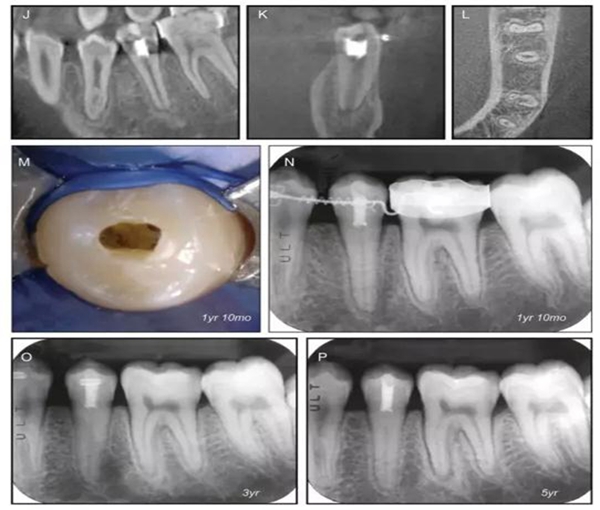

原則上年輕恒牙的牙髓治療應(yīng)盡可能以保存活髓的方式以便不影響牙根繼續(xù)發(fā)育。本文3個(gè)病例均描述了根尖尚未發(fā)育完成的下頜前磨牙被確診為牙髓壞死伴有大面積根尖病損,治療過(guò)程中在根管內(nèi)發(fā)現(xiàn)了部分活髓,而采用活髓切斷后都取得了很好的療效。